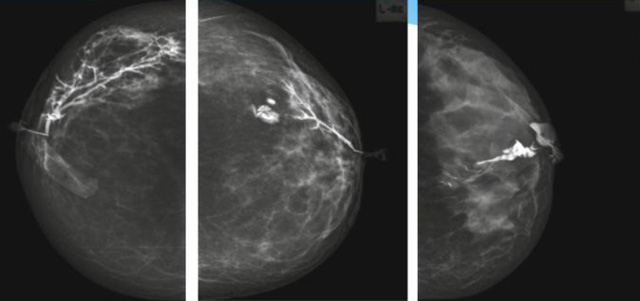

乳腺導(dǎo)管內(nèi)乳頭狀瘤分為以下兩個(gè),位于乳暈區(qū)大導(dǎo)管的中央型乳頭狀瘤,起源于末梢導(dǎo)管小葉單位的外周型乳頭狀瘤。外周型乳頭狀瘤常常沒(méi)有明顯的的臨床表現(xiàn),常因X線或乳腺超聲設(shè)備檢查發(fā)現(xiàn)。重點(diǎn)要關(guān)注的是中央型乳頭狀瘤,發(fā)生于任何年齡的女性,以40~50歲者居多。它表現(xiàn)為:單側(cè)乳頭溢液,特別是血性溢液少數(shù)病人可在乳暈區(qū)觸及腫塊。從病理學(xué)上面講表現(xiàn)為導(dǎo)管上皮和間質(zhì)增生形成有纖維脈管束的乳頭狀結(jié)構(gòu)。這是它一個(gè)病理學(xué)上的表現(xiàn)。它的超聲表現(xiàn)為:病變導(dǎo)管囊狀擴(kuò)張呈無(wú)回聲,內(nèi)可見(jiàn)乳頭狀低回聲或中等回聲。乳暈處的導(dǎo)管擴(kuò)張,管腔內(nèi)可見(jiàn)邊界清楚的,低回聲實(shí)性結(jié)節(jié)。外周型導(dǎo)管內(nèi)乳頭狀瘤可,表現(xiàn)擴(kuò)張為為低回聲的實(shí)性結(jié)節(jié),CDFI:部分腫瘤可顯示為軸心性的看到血流信號(hào)。乳腺增生癥:可見(jiàn)導(dǎo)管擴(kuò)張,內(nèi)無(wú)乳頭狀實(shí)性回聲,導(dǎo)管內(nèi)乳頭狀癌:囊內(nèi)乳頭狀癌病變較大,不規(guī)則,厚基底,血流豐富。以囊性為主的混合回聲,形態(tài)不規(guī)則,內(nèi)見(jiàn)實(shí)性低回聲實(shí)性低回聲可見(jiàn)少量血流,病理為囊內(nèi)乳頭狀癌。

乳腺超聲設(shè)備檢查的價(jià)值在哪里呢?它可以檢查發(fā)現(xiàn)乳暈周圍的各種病變,對(duì)于單側(cè)乳頭溢液、血性溢液的患者,超聲是首選的影像學(xué)檢查方法。注意:導(dǎo)管內(nèi)乳頭狀瘤可合并不典型增生或,導(dǎo)管內(nèi)乳頭狀癌,手術(shù)前懷疑時(shí)候,就應(yīng)該手術(shù)切除而不是用微創(chuàng)手術(shù)。